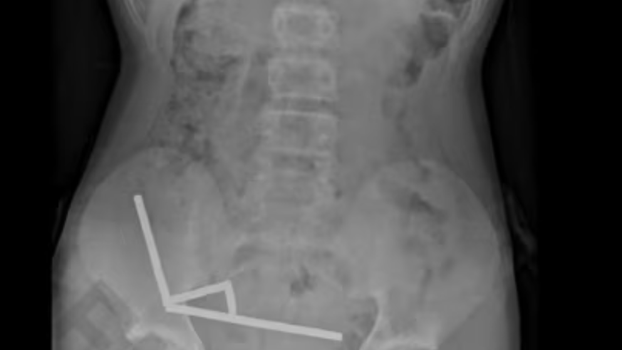

Rendgenska snimka abdomena otkrila je zastrašujući prizor - magneti su se unutar dječakovih crijeva grupirali u četiri kompaktne linije...

Rendgenska snimka abdomena otkrila je zastrašujući prizor – magneti su se unutar dječakovih crijeva grupirali u četiri kompaktne linije.

"Činilo se da se nalaze u odvojenim dijelovima crijeva koji su se slijepili zbog snažne magnetske sile", pojasnili su liječnici. Taj pritisak uzrokovao je nekrozu, odnosno odumiranje tkiva, na četiri mjesta u njegovom tankom i slijepom crijevu.